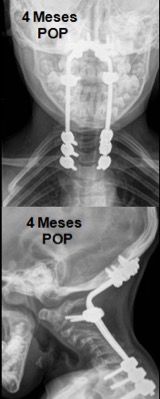

- Figura 14. 4 meses postoperatorio. Fusión posterior instrumentada occipito - torácico